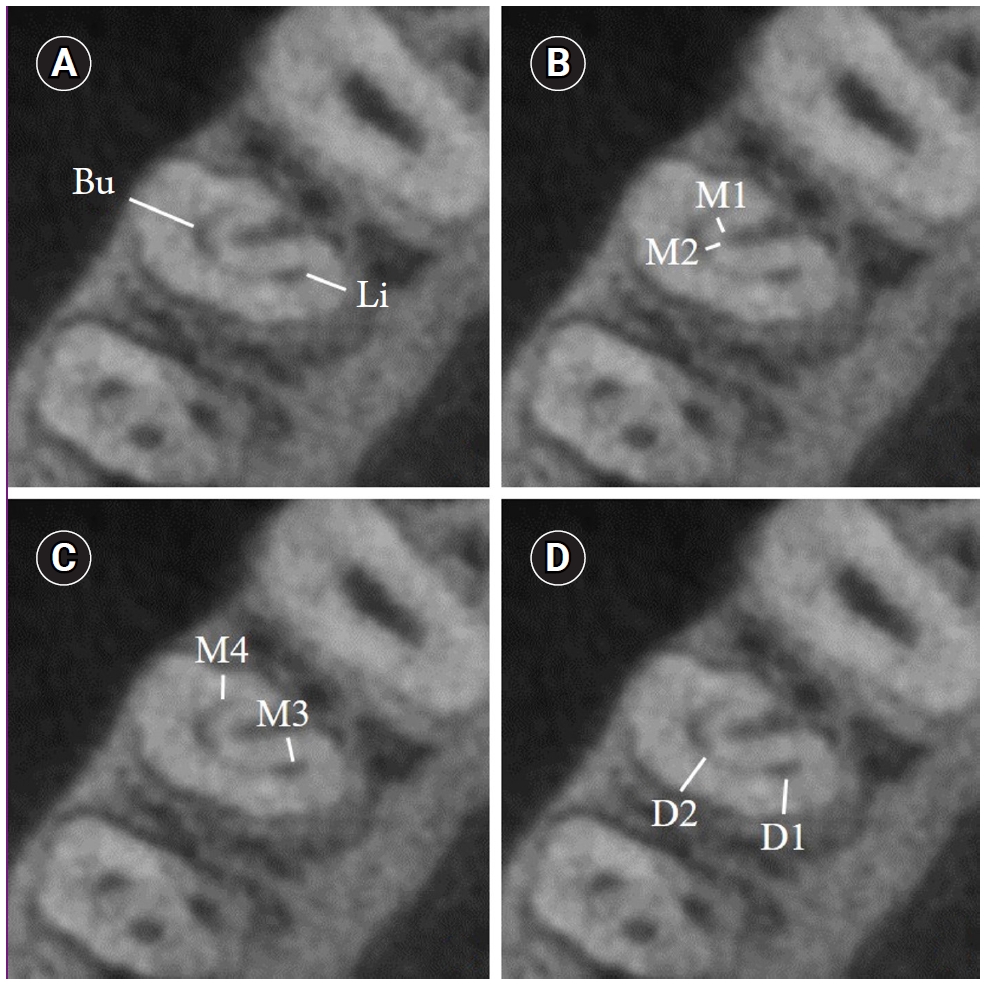

Dentin thickness measurements were made on eight separate dentin walls at all root levels, demonstrating a C-shaped canal configuration. For each root level presenting with C1 or C2 configuration, primarily, thicknesses of buccal (Bu), lingual (Li), distal (D), and mesial (M) walls were measured. Then additional thickness measurements were done at both buccal and lingual canal walls as the distances between: (1) mesial end of the buccal canal and the external root surface facing the radicular groove (M1), (2) distal end of the buccal canal and the external root surface facing the radicular groove (M2), (3) lingual canal and the external mesial root surface facing the radicular groove (M3), (4) mesial end of the buccal canal and external mesial root surface (M4), (5) lingual canal and external distal root surface (D1) and (6) distal end of the buccal canal and the external distal root surface (D2) (Figure 3) [12].

Axial cone-beam computed tomography images showing (A) the root dentin thickness measurements of buccal (Bu) and lingual (Li) walls, (B) mesial and distal ends of the buccal canal facing the radicular groove (M1, M2), (C) between mesial ends of lingual and buccal canals and the external mesial root surface (M3, M4) and (D) between distal ends of lingual and buccal canals and external distal root surface (D1, D2).